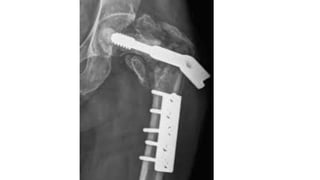

Complication

•